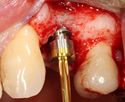

A series of slow-speed drills create and gradually enlarge a site in the jaw for the implant to be placed. The hole is called an osteotomy.

Once the bone is exposed, a series of drills create and gradually enlarge a site (called an osteotomy) for the implant to be placed.